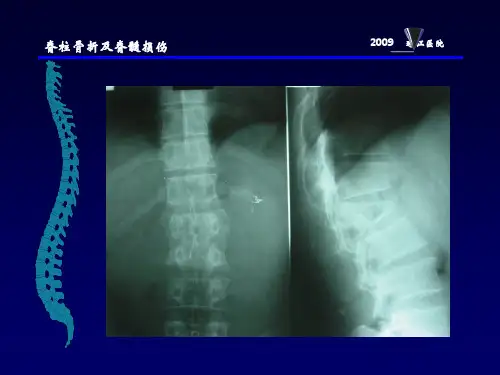

脊柱骨折及脊髓损伤病人的护理脊柱骨折是一种比较严重的创伤,患者多为年轻人,脊柱骨折的病变不仅限于骨组织的损伤,腰背肌韧带也可发生撕裂,脊髓神经也可能受伤。

脊柱骨折又称脊椎骨折,约占全身骨折的5%—6%,最常见的合并症是脊髓损伤,常造成截瘫。

稳定型骨折:单纯压缩性骨折,椎体压缩不超过原高度的不稳定型骨折:椎体压缩超过原高度的以上的压缩性骨折,椎体粉碎性骨折,椎体骨折合并脱位。

护理评估:1、健康史2、身心状况3、诊断检查病因:间接暴力:占绝大多数直接暴力:1.受伤局部疼痛和活动受限2.损伤部位的棘突明显压痛;胸、腰段损伤时,常有局部肿胀和后突畸形3.有脊髓损伤的相应症状和体征4.严重损伤可有休克及合并症影像学检查有助于明确诊断,确定损伤部位、类型和移位情况,X线摄片是首选的检查方法护理诊断:一、躯体移动障碍与疼痛及神经损伤有关与脊柱骨折可。

【症状】一、脊柱骨折1、有严重外伤史,如高空落下、重物打击头颈或肩背部、塌方事故、交通事故等。

2、病人感受伤局部疼痛,颈部活动障碍,腰背部肌肉痉挛,不能翻身起立。

骨折局部可扪及局限性后突畸形。

1 临床特征根据受伤的部位及程度不同,临床表现亦不一致。

合并脊髓损伤后可有神经系统的改变。

1.2胸腰段骨折或骨折脱位表现为局部疼痛,腰背肌痉挛,不能直立,翻身困难,由于腹膜后血肿对自主神经的刺激,肠蠕动减弱,出现腹胀、腹痛、便秘等。

若伴有脊髓神经损伤,则出现不同平面的不完全性或完全性截瘫。

脊柱骨折和脊髓损伤患者的护理常规一、脊柱骨折脊柱骨折十分常见,约占全身骨折的6.4%,其中胸腰段骨折最多见。

脊柱骨折可并发脊髓或马尾神经损伤,特别是颈椎骨折一脱位合并有脊髓损伤最高可达70%,能严重致残甚至丧失生命。

中柱和后柱组成椎管,容纳了脊髓和马尾神经,该区的损伤可以累及神经系统,特别是中柱损伤,碎骨片和髓核组织可以突入椎管的前半部而损伤脊髓,因此对每个脊柱骨折病例都必须了解有无中柱损伤。

胸腰段脊柱(To〜12)处于两个生理弧度的交汇处,是应力集中之处,也是常见骨折之处。